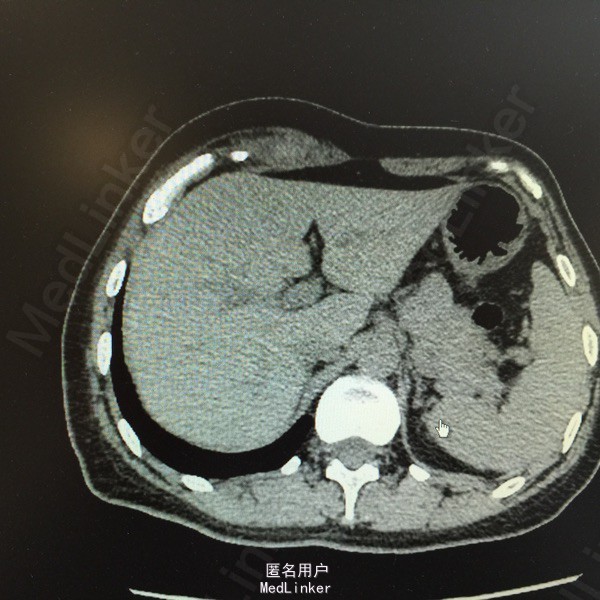

主诉:腹痛、发现腹部肿物15天。 现病史:患者于15天前因运动后突发腹痛,为持续性胀痛,伴停止排气,无恶心、呕吐,后觉疼痛缓解,并发现腹部肿物,压痛明显。当时于外院行超声:右上腹患者所指处肌层见无回声,约8*6cm大小,形态规则,边界清。现患者无诉疼痛,自觉肿块变小,为进一步诊治,收入我科。 既往史、家族史均无特殊。 查体:全腹软,右上腹近季肋部可触及一5*2cm包块,质软,活动差,压痛明显,周围皮肤无红肿、无溃烂。余无特殊。 辅助检查: 超声:患者右上腹腹壁层内肌层后方见无回声,大小约5.4*2.3cm,形态规则,边界尚清,内见少许分隔。考虑右上腹腹壁内囊性包块。 CT:右上腹季肋部腹直肌鞘内梭形软组织密度影,病变中央密度高,约65HU,边缘密度稍低,约33HU。印象:右上腹腹直肌鞘内梭形高密度影,血肿不除外。 大家考虑?